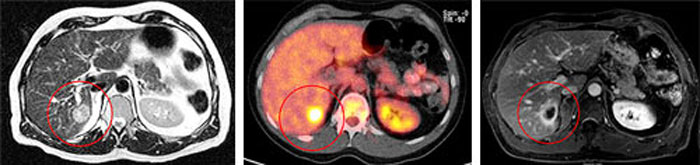

Виды роста злокачественных опухолей. Рост злокачественных новообразований. Злокачественные опухоли характеризуются. Форма злокачественной опухоли. ПЭТ кт онкология глиома. Метастазы в печени на ПЭТ кт.

ПЭТ кт онкология глиома. Метастазы в печени на ПЭТ кт. Лимфангиома брыжейки кт. Лимфома брыжейки тонкой кишки кт.

Глиома внутримозговая кт. Метастатические опухоли мозга. ПЭТ кт томограмма. Кт, ПЭТ И ПЭТ/кт. ПЭТ кт с контрастом. Скопление контраста ПЭТ кт.

ПЭТ кт томограмма. Кт, ПЭТ И ПЭТ/кт. ПЭТ кт с контрастом. Скопление контраста ПЭТ кт. Метастатическое поражение печени. Метастатические опухоли печени. Злокачественные образования печени.